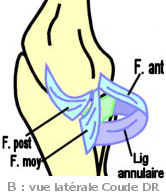

(Schéma

A) Le ligament collatéral ulnaire (old.

lig. lat. interne ou LLI) est le plus puissant. C'est un

éventail fibreux qui irradie de la face antérieure de l'épicondyle

médial en 3 faisceaux (F. Antérieur et F. Moyen, vers le processus

coronoïde de l'ulna / F. Postérieur vers l'ARR jusqu'à l'olécrâne).

(Schéma

A) Le ligament collatéral ulnaire (old.

lig. lat. interne ou LLI) est le plus puissant. C'est un

éventail fibreux qui irradie de la face antérieure de l'épicondyle

médial en 3 faisceaux (F. Antérieur et F. Moyen, vers le processus

coronoïde de l'ulna / F. Postérieur vers l'ARR jusqu'à l'olécrâne).